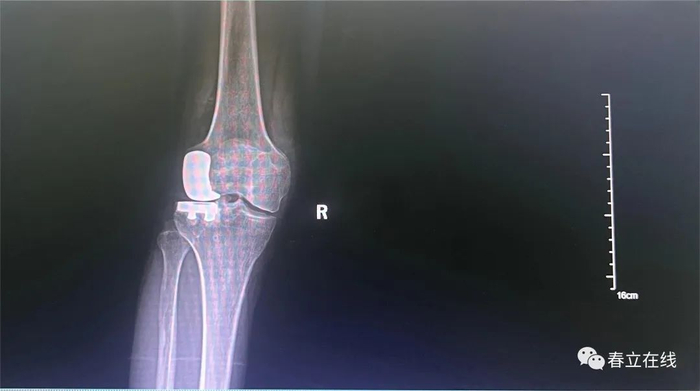

// 术后片

患者右膝关节骨关节炎诊断明确,疼痛症状以外侧为主,MRI提示前外侧间室软骨面全层磨损,内侧间室及髌骨关节软骨完整,前叉韧带信号清晰,体查提示膝关节稳定性尚可,完善术前相关检查检验,排除手术禁忌后拟行“右膝关节单髁置换术”。